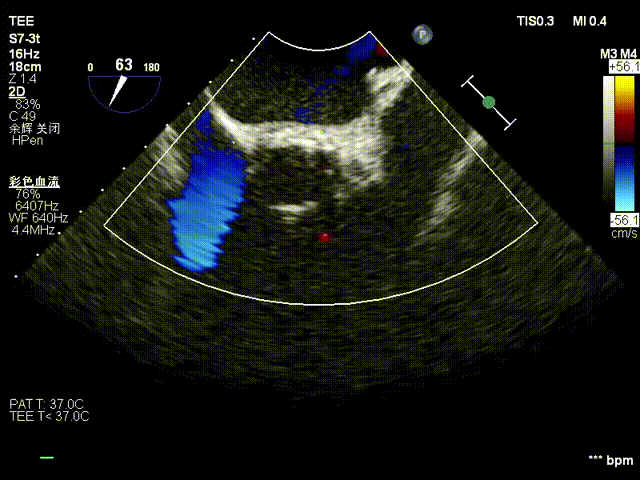

•超声检查:主动脉瓣上血流Vmax=5.35m/s,瓣口面积0.6~0.7cm²,主动脉瓣反流面积6cm²,EF值62%,诊断为“重度主动脉瓣狭窄,中量主动脉瓣反流”。

超声多切面评估,瓣膜植入位置理想,血流动力学改善明显